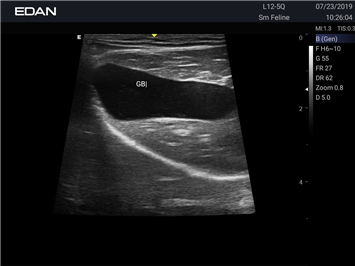

Ветеринарный ультразвук одним нажатием. Система Acclarix AX2 VET разработана с целью обеспечить бескомпромиссную производительность по доступной цене. Наличие уникальных двойных аккумуляторов в легком корпусе массой 4,5 кг из магниевого сплава позволяет системе Acclarix AX2 VET удовлетворять все потребности ветеринарных исследований, сохранив низкую стоимость.

EDAN Acclarix AX2 VET представляет собой специализированную ветеринарную ультразвуковую систему, сочетающую высокую производительность с доступной ценой. Благодаря продуманной конструкции и передовым технологиям, система обеспечивает качественную диагностику животных различных видов.

• Высокое разрешение для детальной диагностики

• Улучшенная визуализация глубоко расположенных органов

B-режим, Двухмерное сканирование:

Да